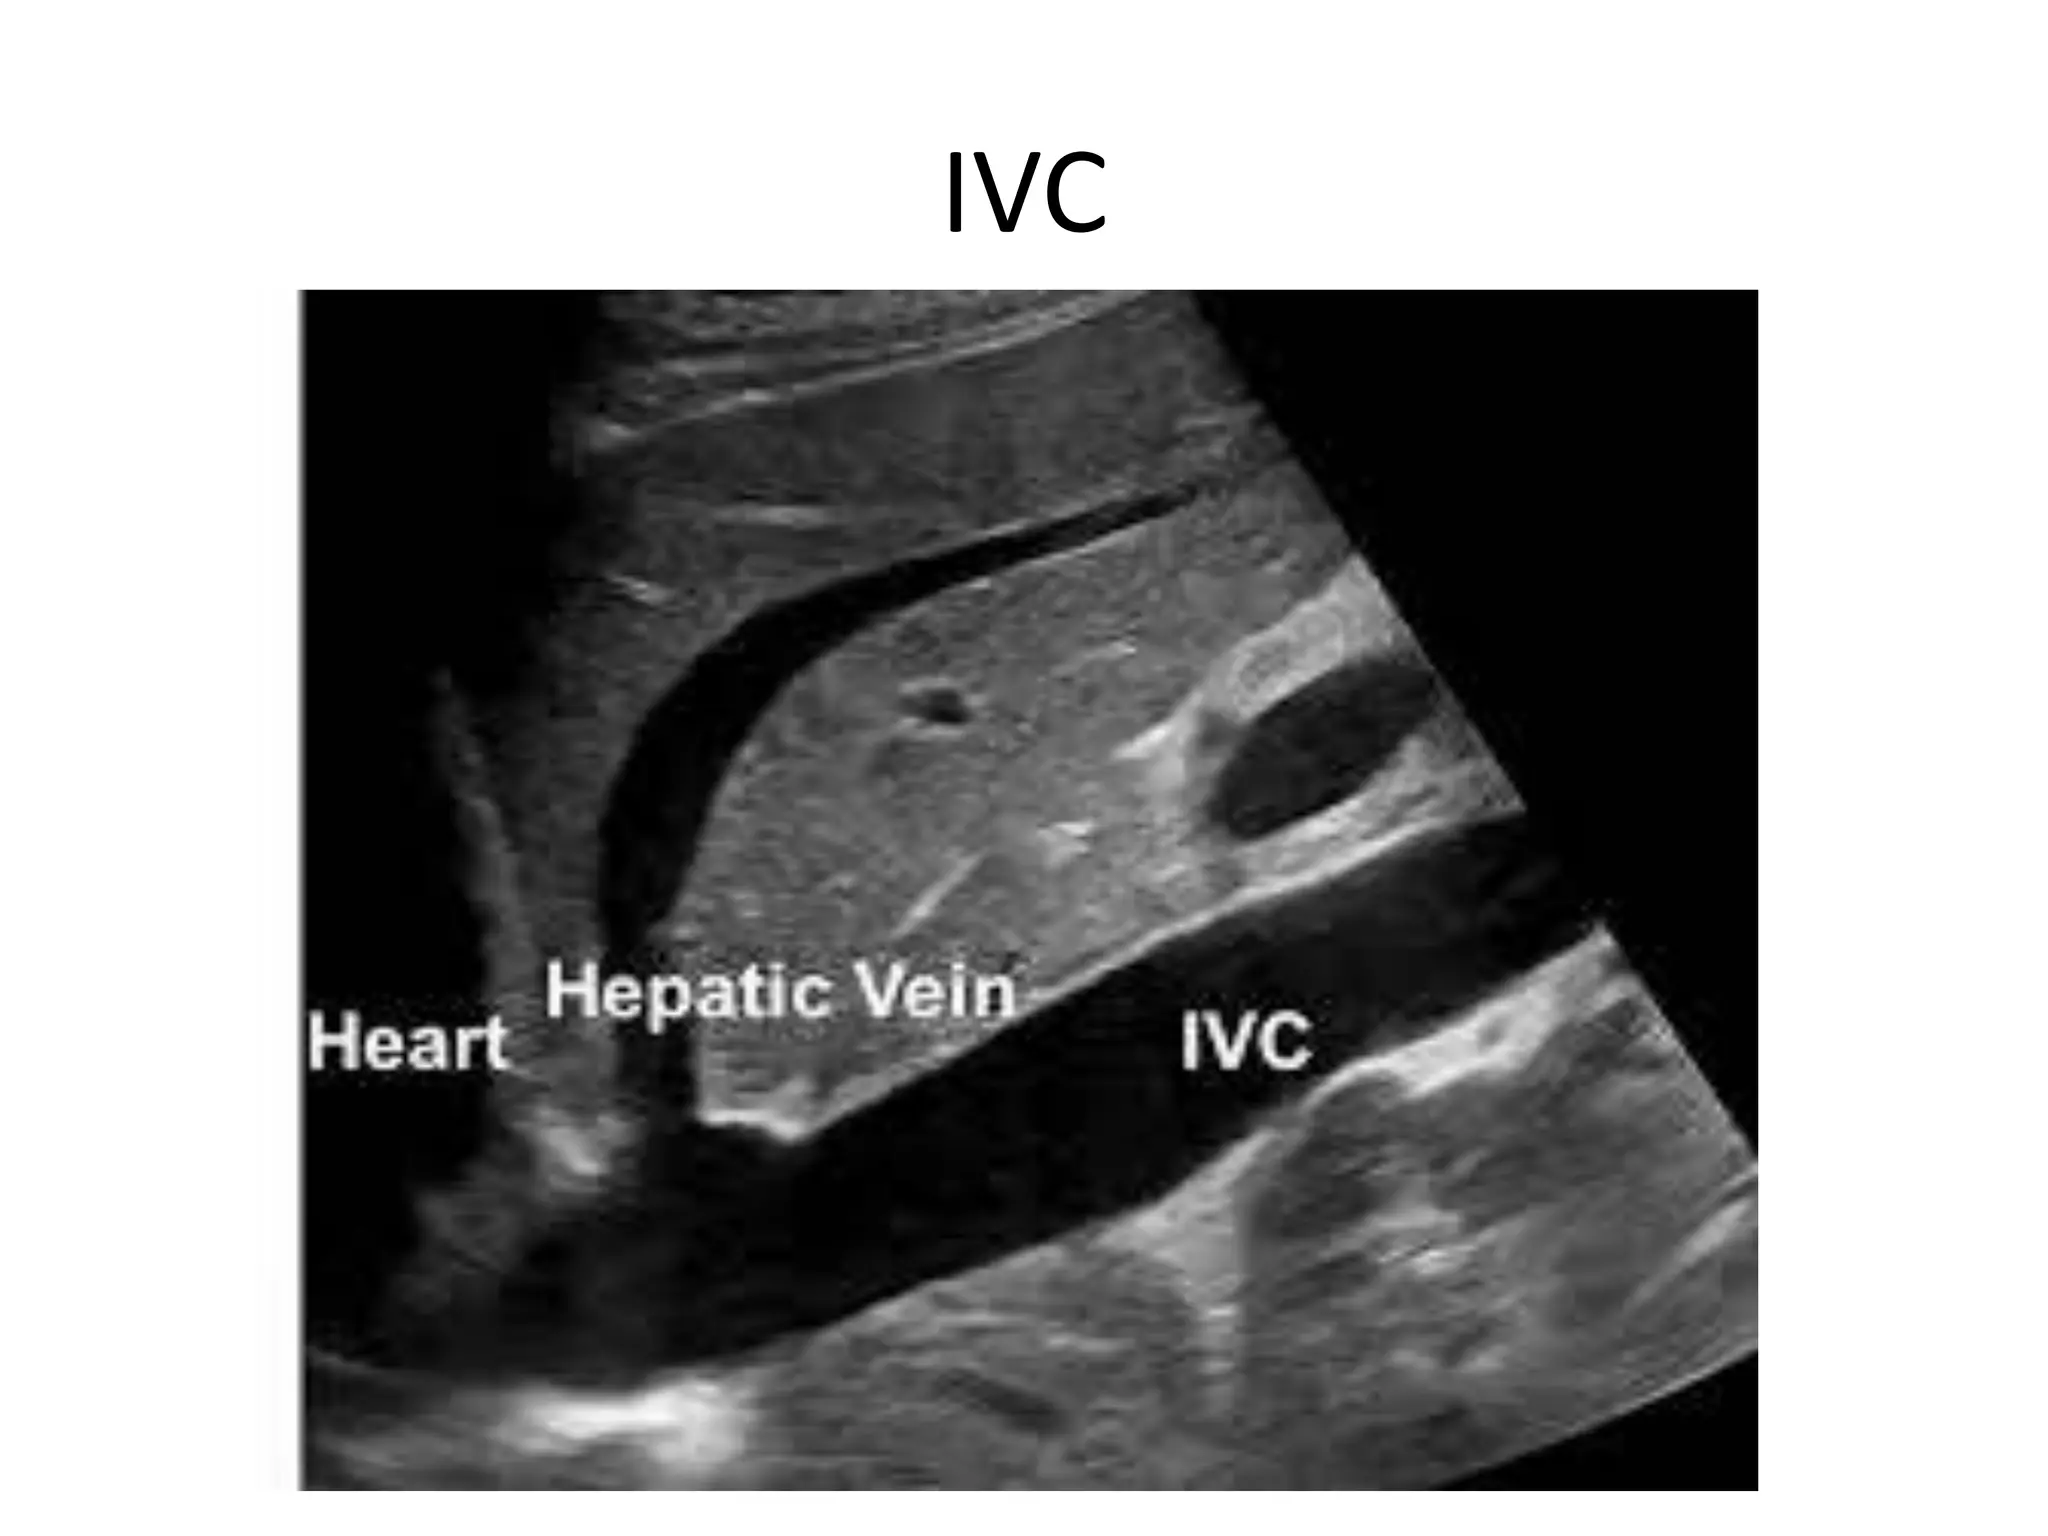

IVC